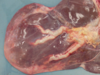

Describe these lesions. What disposition would you apply?

Multiple, pale, randomly distributed, 2-5mm, non-raised, chronic (as they are pale non-raised) infarcts - nephritis

Reject the kidneys - check for evidence of uraemia, oedema or abnormal smelling urine